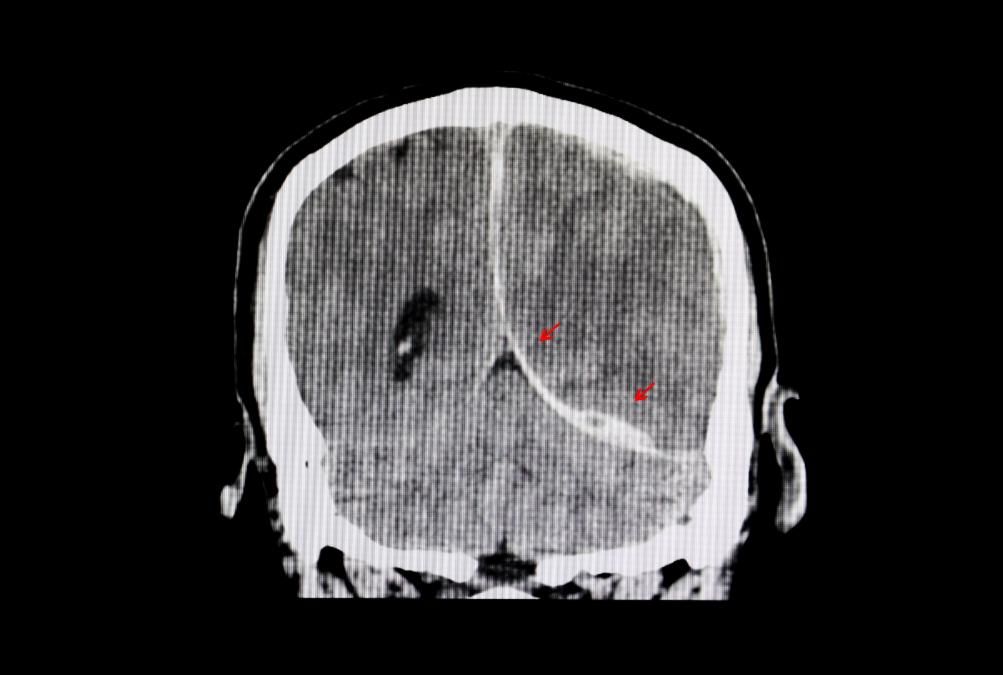

The Lingering Effects of Past Brain Injuries

Traumatic brain injuries (TBIs) can leave lasting impacts, even years after the initial event. Symptoms like brain fog, headaches, memory loss, or difficulty concentrating may persist, leading many to feel stuck.

But the truth is, the brain has an incredible ability to heal and adapt through neuroplasticity—the ability to rewire and create new pathways. The first step is recognizing that it’s not too late to seek solutions. Targeted therapies, exercises, and personalized care plans can make a significant difference, helping individuals reclaim their focus, energy, and confidence.